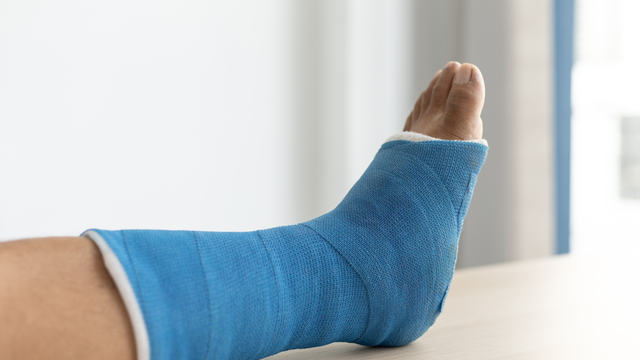

Gãy xương